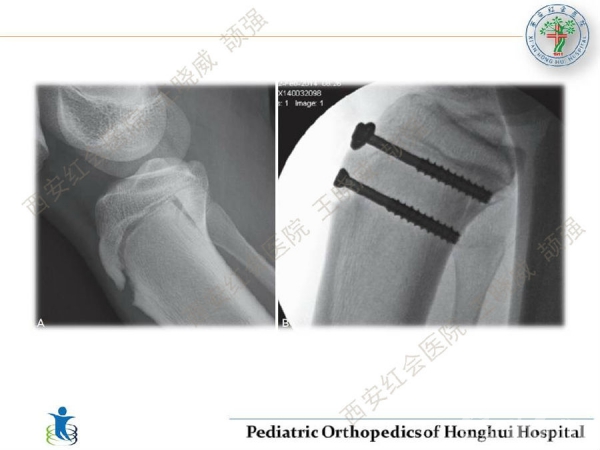

儿童胫骨结节撕脱骨折的分型与治疗

胫骨结节撕脱骨折并不常见,多发生在青少年体育运动中,临床诊疗过程中需要针对骨骺发育及关节内骨折进行综合考量,如何规避损伤带来的骨骺损伤,同时恰当的处理关节内骨折,是小儿骨科医生临床上面对此类患儿时需要关注的问题